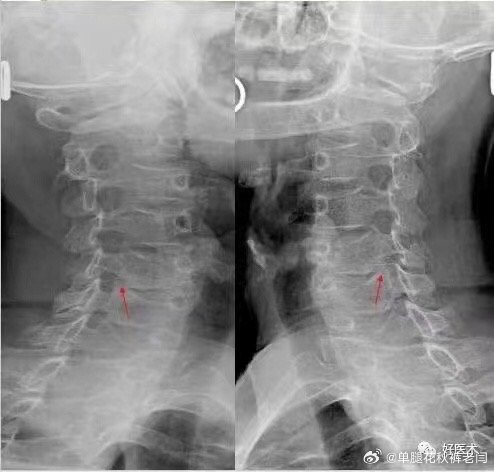

颈椎病不一定都是脖子疼

脑梗塞、眩晕、肩周炎、甲状腺疾病、哮喘、咽喉问题及咳嗽,手指、手臂麻木酸疼,心血管病等颈椎问题值得大家关注

我3-7颈椎间盘突出,比较轻,让我没事的时候就多抬抬头